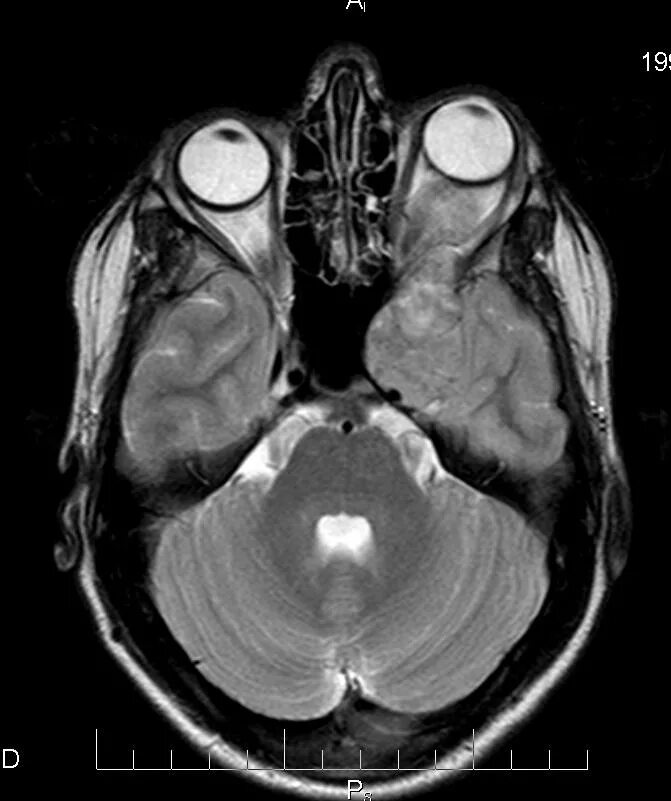

Мрт орбит и зрительных нервов